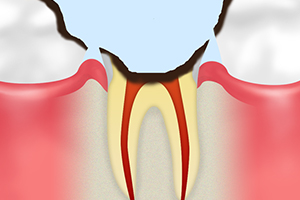

C3 神経に達した虫歯

|

虫歯が神経にまで達した状態です。何もしていなくても常に激しい痛みがあるため、早めの治療が必要です。 | 虫歯菌によって汚染された神経を除去する「根管治療」という治療を行い、被せ物で歯の見た目と機能を補います。 |

C4 歯根に達した虫歯

|

虫歯菌が神経の奥にある歯根まで進行した状態です。神経が完全に死んでしまい痛みは出なくなりますが、膿が出るようになると激痛が走り、治療も長期化します。 | 根管まで虫歯が進行すると、ほとんどの場合で抜歯が必要になります。歯を抜いた部分は入れ歯やインプラントで補います。 |